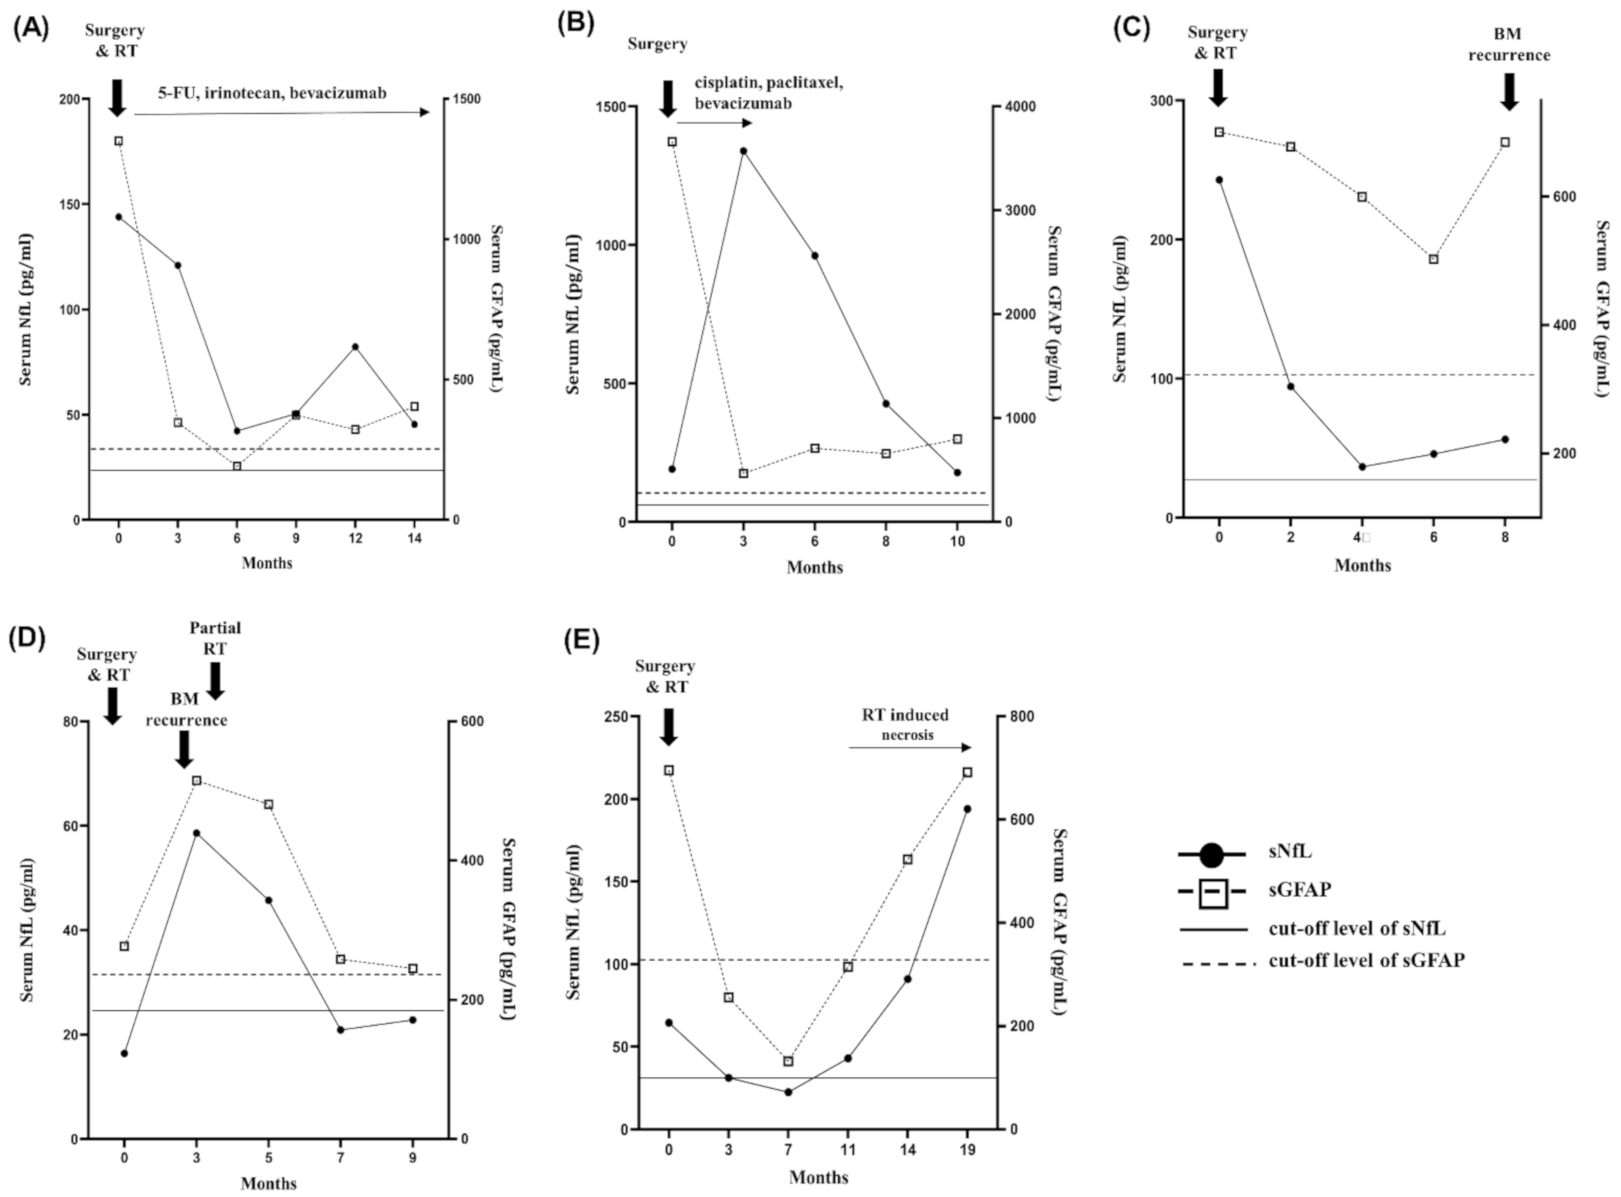

2.5. Longitudinal Follow-Up